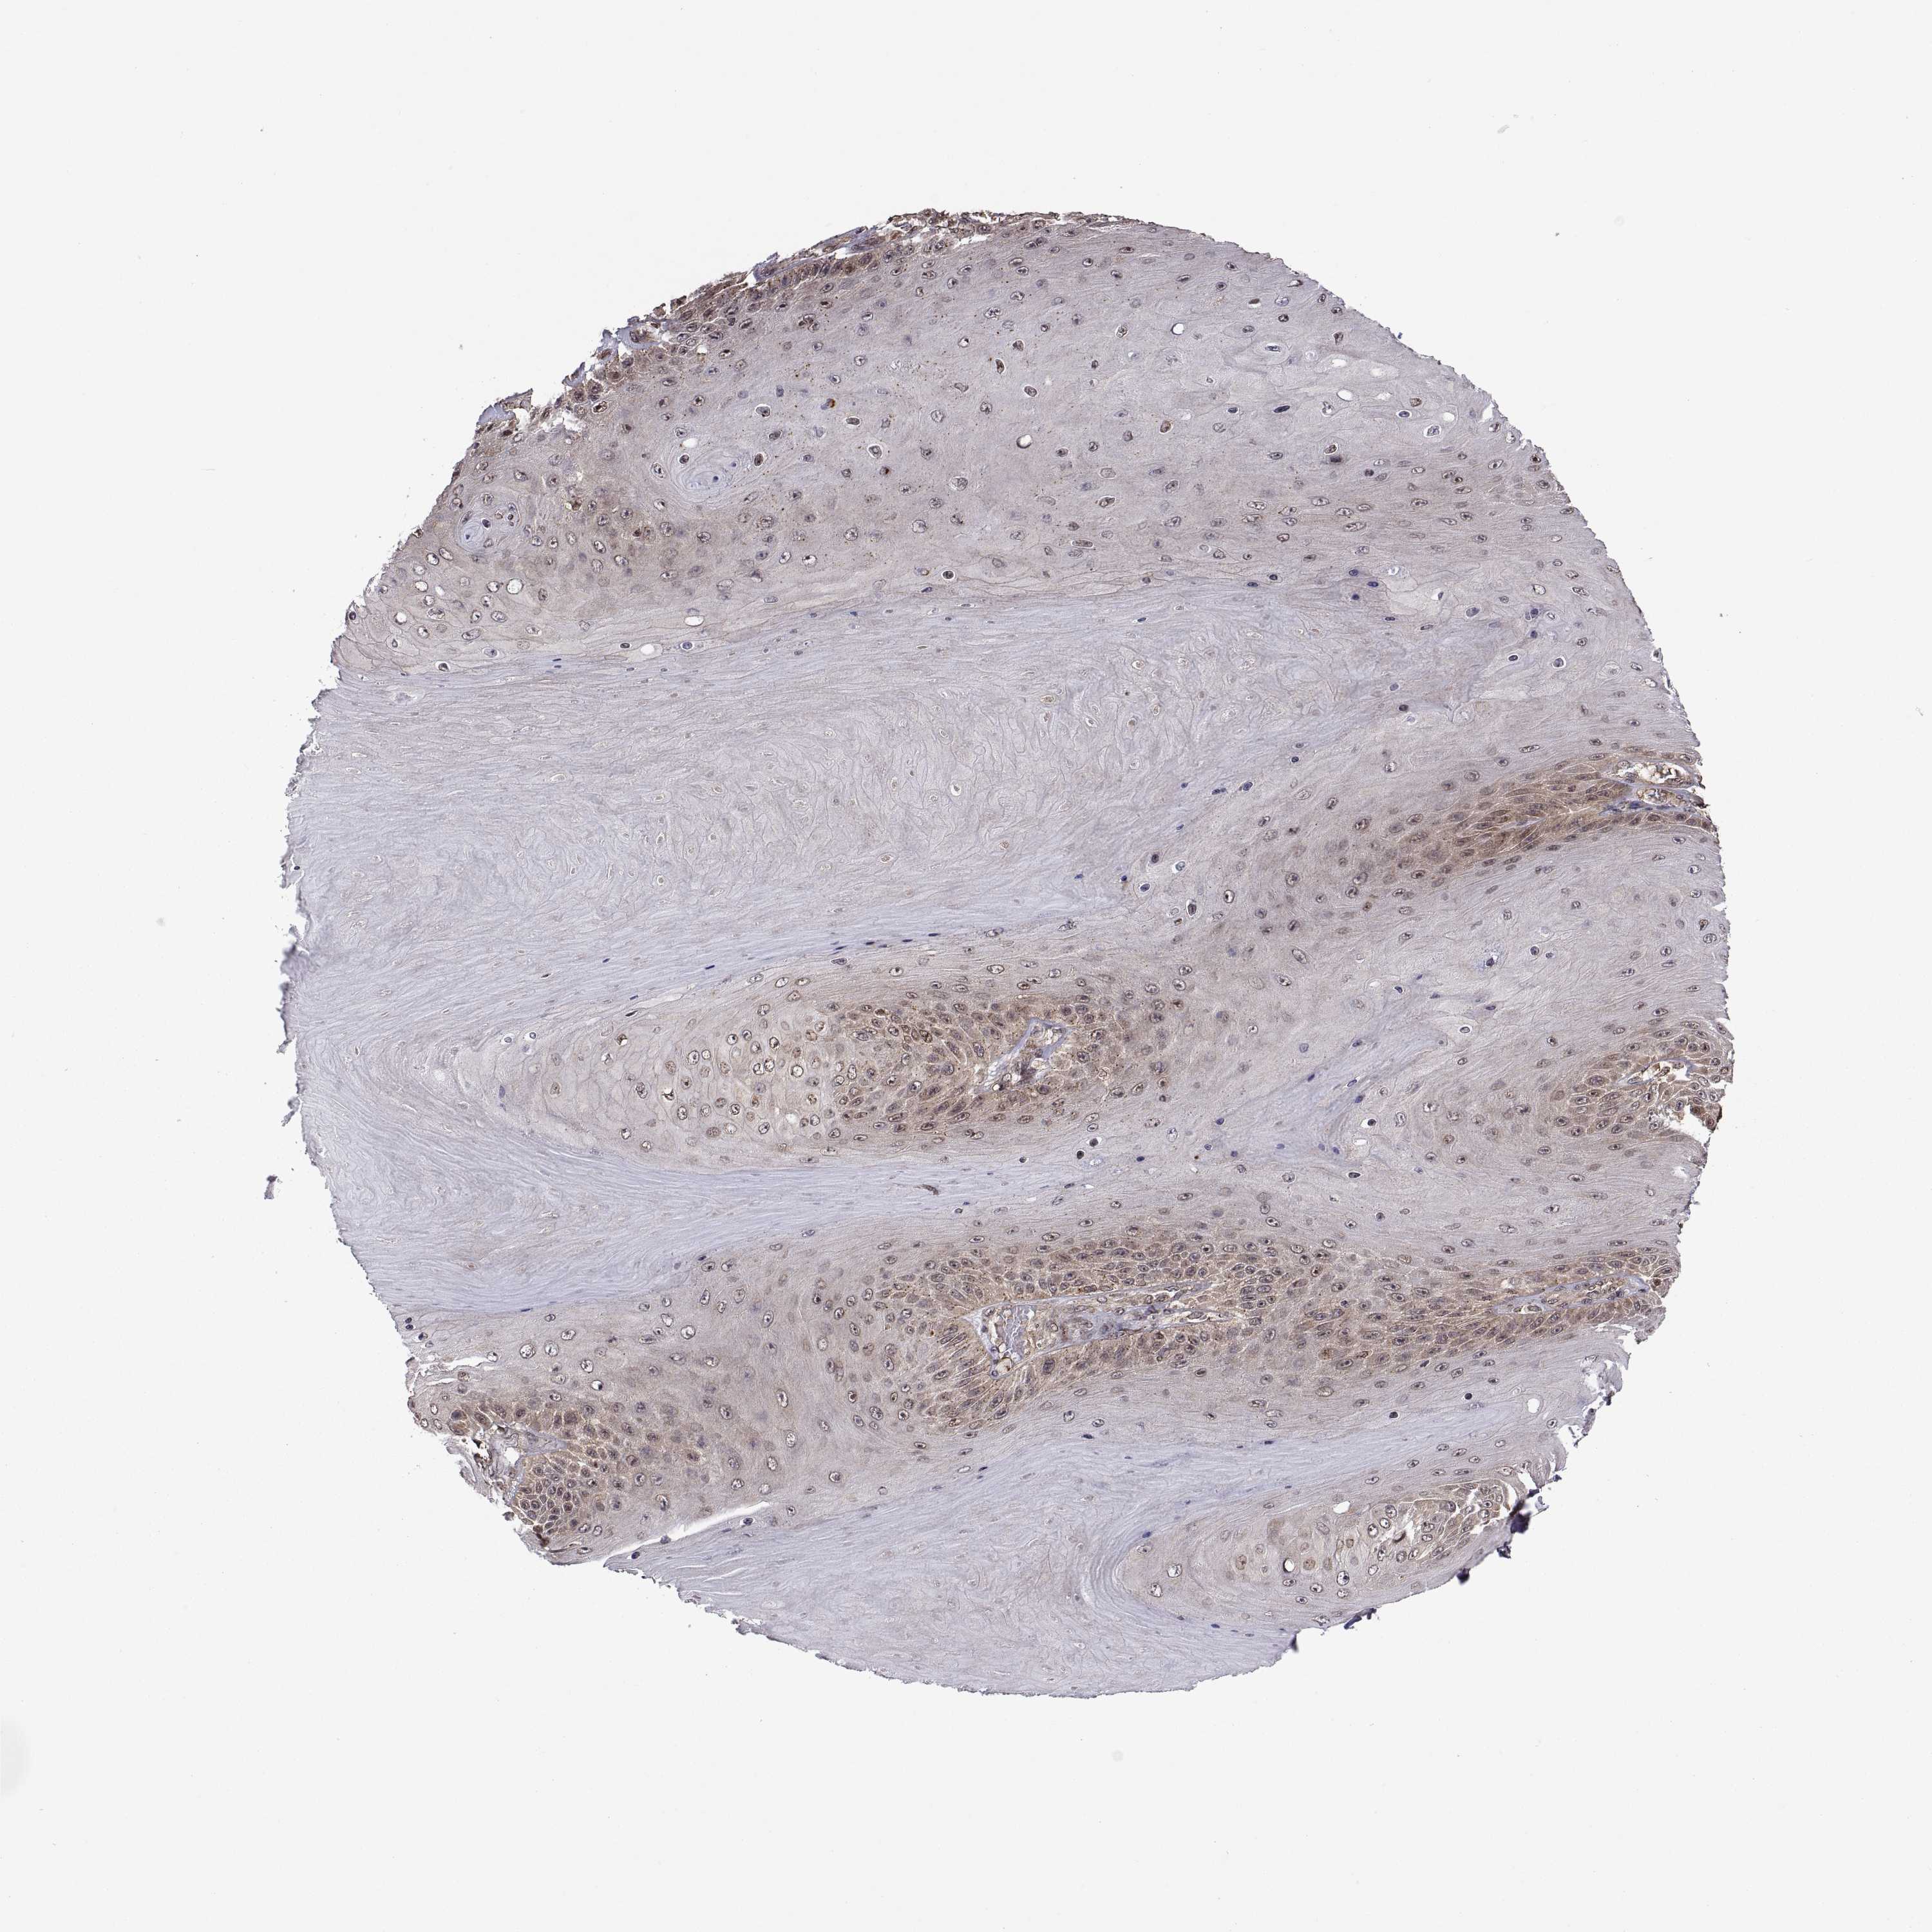

CANCER SKIN CANCER Show tissue menu

Basal cell and squamous cell cancer

SKIN CANCER - Protein expressioni

A mouse-over function shows sample information and annotation data. Click on an image to view it in a full screen mode. Samples can be filtered based on level of antibody staining by selecting one or several of the following categories: high, medium, low and not detected. The assay and annotation is described here.

Antibody stainingi

Antibody staining in the annotated cell types in the current human tissue is reported as not detected, low, medium, or high, based on conventional immunohistochemistry profiling in selected tissues. This score is based on the combination of the staining intensity and fraction of stained cells.

Each image is clickable and will lead to virtual microscopy that enables deeper exploration of all samples and also displays staining intensity scores, fraction scores and subcellular localization as well as patient and tissue information for each sample.

Antibody HPA072244

Staining

High

Medium

Low

Not detected

Intensity

Strong

Moderate

Weak

Negative

Quantity

>75%

75%-25%

<25%

None

Location

Nuclear

Cytoplasmic/membranous

Cytoplasmic/membranous,nuclear

Basal cell carcinoma

Squamous cell carcinoma, NOS